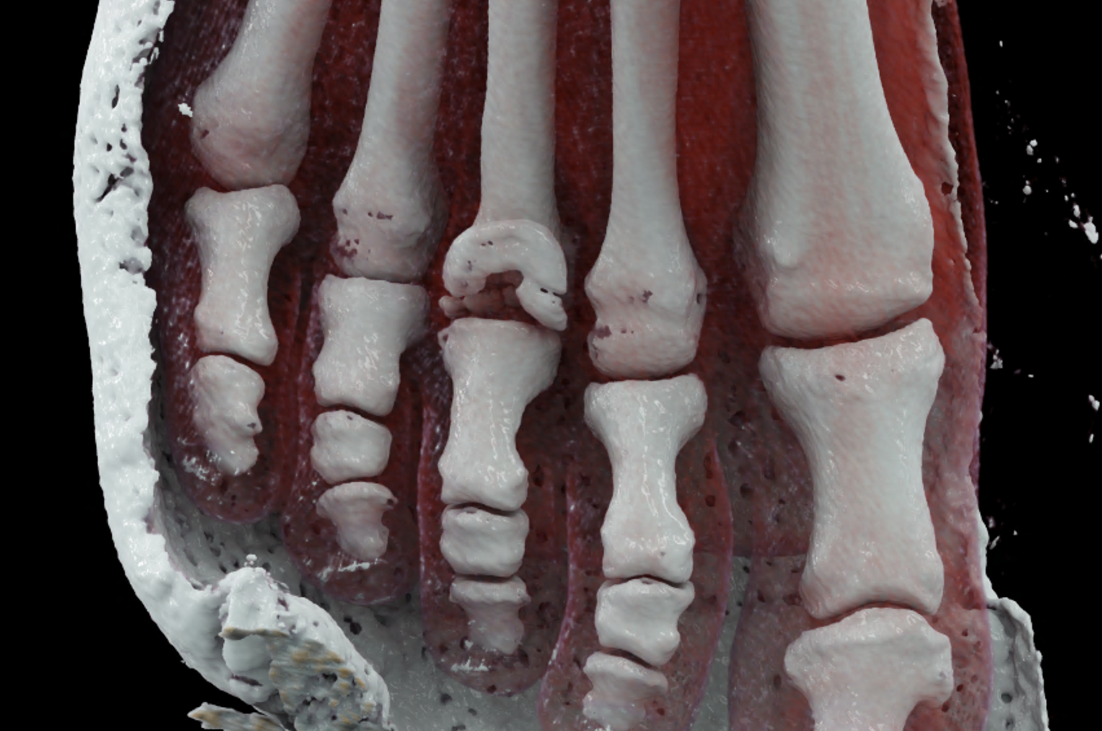

Freiberg-Koehler disease is aseptic necrosis of the head of the second or third metatarsal bone. It is more common in girls during puberty and skeletal maturation, when necrosis of the head occurs, followed by its fragmentation and subsequent deformity of the front part of the foot and the formation of pressure sores. In the acute stage, swelling and pain may occur in the area of the transverse flat arch of the foot. However, it very often progresses without any symptoms and only begins to manifest itself at a later age in connection with transverse flatfoot, with pain and pressure sores under the metatarsal heads in the front part of the foot. In the acute stage in growing children, pain in the front of the foot usually occurs after and following exertion. CT scans show fragmentation and dorsal subluxation of the distal fragments in aseptic necrosis of the metatarsal head more clearly than plain X-rays. Necrosis manifests itself in a changed structure and, in later stages, a significant change in shape; often, significant destruction of the metatarsal head can be seen.

When using ultra-high resolution CT with the smallest possible detector element, even the smallest details of bone changes can be visualized using photon-counting CT. By reconstructing images with a width of 0.2 mm and an overlap of 0.1 mm, there is a significant improvement in resolution in the planes of the reconstructed images in the metatarsal axis in the long axis of the foot, but also in the plane perpendicular to it, which better displays the metatarsophalangeal joint in the laterolateral direction.

volume rendered reconstructions